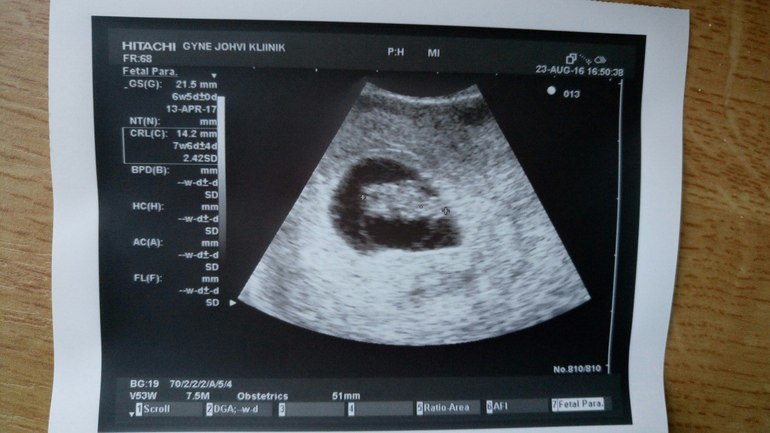

Вчера была на повторном узи у Г, малыш соответствует сроку, мы уже 14,2 мм (8 недель от зачатия и 10 акушерских) и сердечко у нас стучит 169 уд/мин!!!

Самого малыша, к сожалению еще пока не рассмотришь тем более у моего Г узи-не очень,получилось просто пятнышко

С удачным походом! Да,узи оставляет желать лучшего, ну немного подождать и уже хорошо все увидите! Ой,а может я что-то путаю,на узи срок отмечен 7,6,это ведь акушерских,почему 10 тогда?

7.6 сказал эмбриональный срок)

Я спросила а по какому мне ориентироваться,говорит ну считай 10-ая неделя и впринцепи по М и всем подсчетам подходит

И по всем табличкам по размеру подходим тоже)